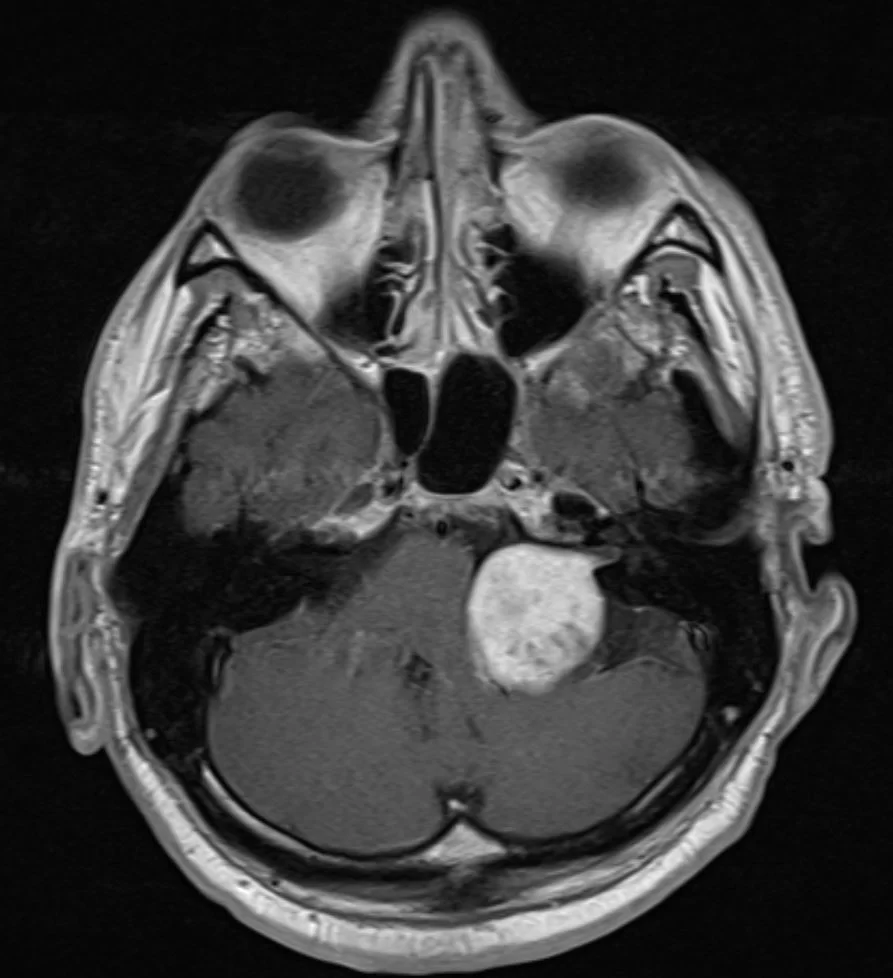

Μηνιγγίωμα Ινιακού Τρήματος

Ασθενής γυναίκα, 54 ετών με διαταραχή βάδισης. Ο προεγχειρητικός έλεγχος ανέδειξε μηνιγγίωμα της κρανιοαυχενικής συμβολής με εγκολεασμό σημαντικών αγγειακών και